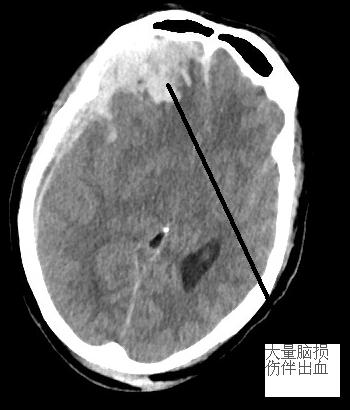

患者沈女士,62歲,4月10日約13時(shí)從高處摔下,家屬趕緊送至我院急診科。經(jīng)CT檢查,提示多發(fā)腦出血后,患者意識(shí)障礙迅速加深,呈昏迷狀態(tài),無(wú)法應(yīng)答。復(fù)查CT后,腦內(nèi)出血明顯增加,出血量較大,環(huán)池變窄,腦干受壓,若病情持續(xù)加重可能會(huì)造成腦干功能受損,甚至影響呼吸、心跳。有急診開顱手術(shù)指征,為取得最佳搶救時(shí)機(jī),及時(shí)告知家屬病情并取得知情同意后,我院神經(jīng)外科一方面積極術(shù)前準(zhǔn)備,另一方面緊急聯(lián)系福醫(yī)大附二院神經(jīng)外科對(duì)接我院當(dāng)值專家研討病情,術(shù)前準(zhǔn)備完善后,隨即送入手術(shù)室,術(shù)中見腦組織膨隆明顯,壓力大,予充分清除血腫后,見腦組織壓力減低。

▲上圖為術(shù)前顱內(nèi)血腫